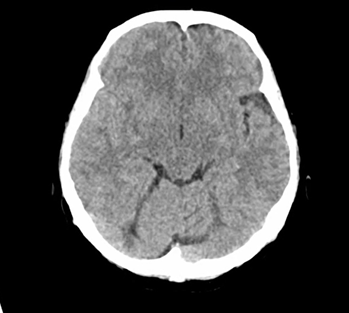

重症筋無力症:「眼瞼下垂の増強」所見(眼瞼下垂の能動的挙上により両側への神経刺激が減少し、対側の眼瞼が弛緩し下垂する所見を認めた症例

23歳男性。1か月前から複視と右側のまぶたの垂れ下がりが出現し、内科外来受診となった。 症状は夕方の方が悪く、ろれつが回りにくいといった症状や、嚥下困難や四肢の…